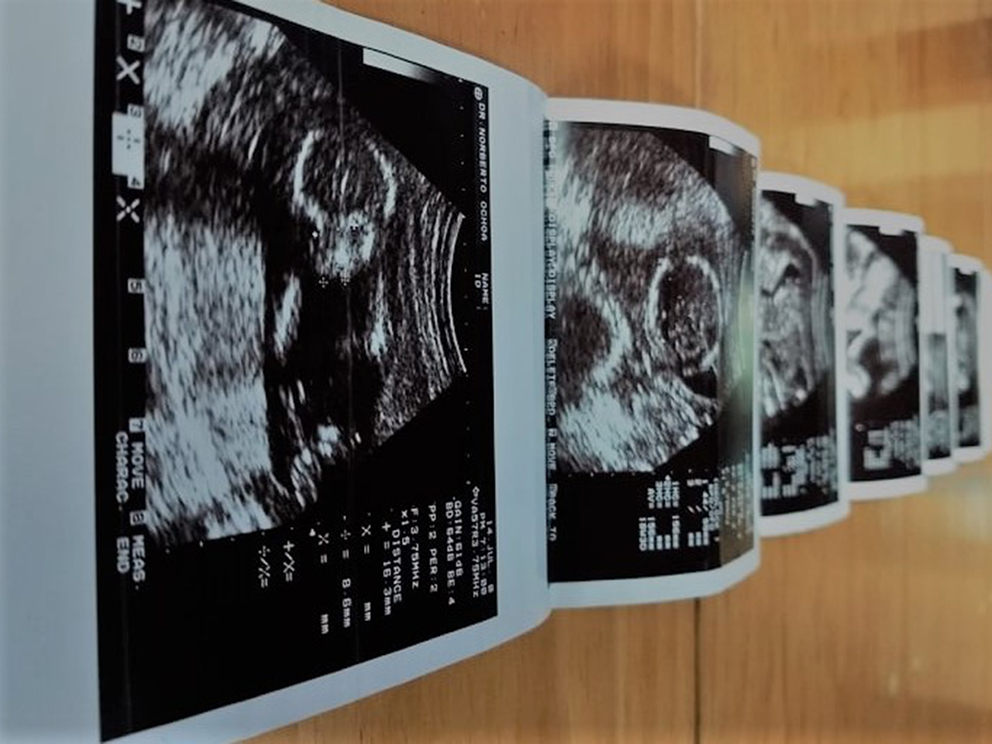

Tu hermanita se murió, le dije a L. Lloró, lloró mucho y no dijo nada. Tengo de Glenda la imagen del ultrasonido y sus cenizas en una cajita de mármol. Todavía no sé si llevar a mi hija al mar o a un lago color té verde. O dejarla conmigo. La psicóloga me ha sugerido hacer algo con ella para cerrar. Qué ocurrencias.